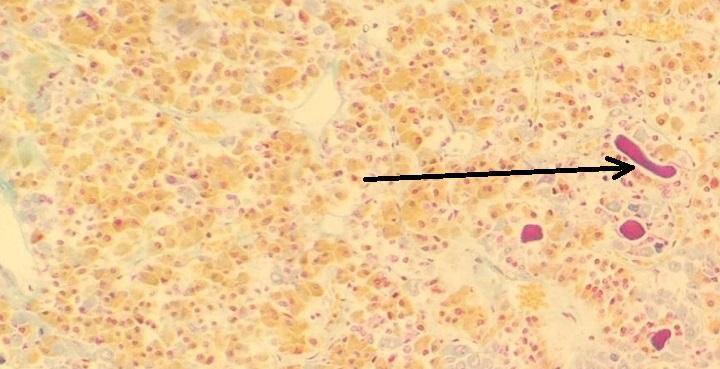

pęcherzyk wypełniony koloidem (przysadka mózgowa - część gruczołowa, barwienie metodą Sliddersa).jpg